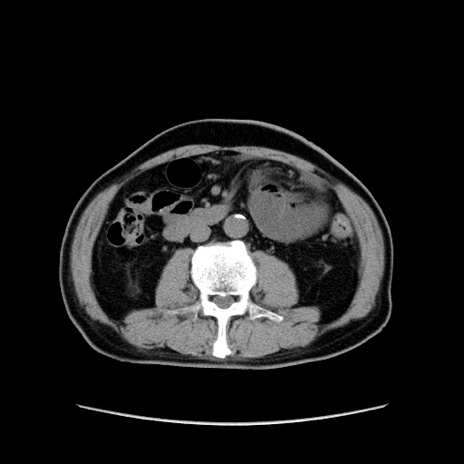

症例24(横断像)

【症例】80歳代男性

【主訴】左側腹部痛、嘔吐

【現病歴】本日早朝より左腹部に痛みあり。昼頃嘔吐認めたため、救急要請。

【既往歴】直腸癌(Mile手術)、胆摘

【身体所見】意識清明、BT 35.9℃、BP 221/93mmHg、SpO2 97%(RA) 、腹部:左ストーマ周囲に限局性の腹部膨隆あり。 膨隆部自発痛・圧痛あり・軟。

【データ】WBC 7700、CRP 0.09